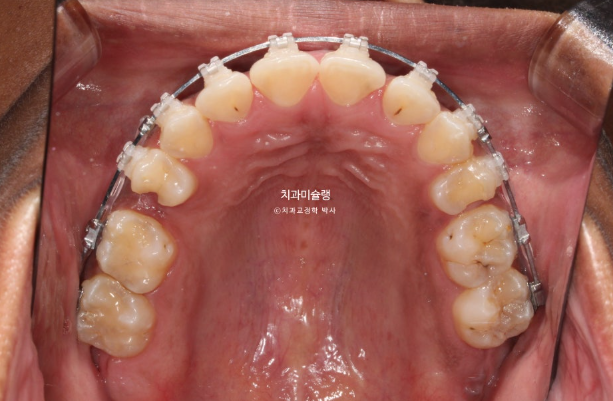

This patient is a foreign individual in their 20s who first visited us in July 2023 for orthodontic treatment.

The patient had previously undergone non-extraction orthodontic treatment but did not wear retainers, resulting in relapse of the anterior teeth. Due to dental caries, several teeth were subsequently lost, leading the patient to seek re-treatment.

In the maxilla, one premolar had decayed to the point where only the root remained.

The patient opted for treatment using Clippy-C bracket orthodontics.